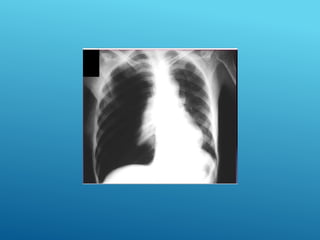

HEMOTÓRAX DERECHO

HEMONEUMOtórax

24/03/2017

HEMOTÓRAX, CONTUSIÓN PULMONAR MASIVA

HEMATOMA PULMONAR

COLAPSO PULMONAR